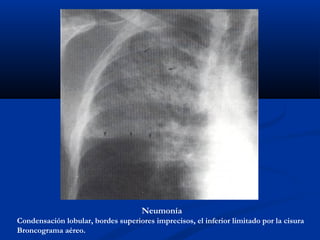

Neumonía

Condensación lobular, bordes superiores imprecisos, el inferior limitado por la cisura

Broncograma aéreo.

1.- Signos radiológicos:

Su tendencia a la coalescencia hace que las lesiones

sean de bordes borrosos y mal definidos, excepto cuando

llegan a una cisura que da nitidez al borde de la lesión.

- Aspecto algodonoso de los bordes.

- Tendencia a la coalescencia.

- Distribución lobar o segmentaria (las cisuras

hacen de límite).

- Distribución en ala de mariposa.

- Broncograma aéreo.

- Aparición y resolución rápida.